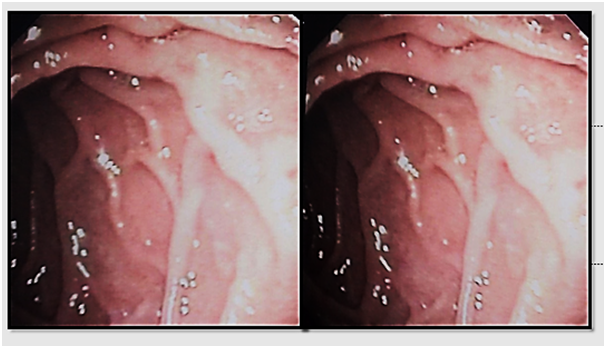

A 53- years old male presenting with chronic diarrhea of 8months duration, his diarrhea was of large volume, frothy in nature with foul odour. It was not related to a specific type of food, persisted during fasting with no diurnal variations. His condition was also associated with significant weight loss. The condition was associated with low grade fever and arthralgia of his both knee and hip joints. After 2months from the onset of his diarrhea he started to develop dizziness and easy fatigability. Physical examination of the patient was unremarkable apart from the pallor. Work up for diagnosing the cause of his diarrhea was done in the form of repeated stool analysis and culture, complete blood count, liver profile, renal profile, electrolytes, ESR, B2 microglobulins, virology (HIV, HBsAg, antiHCVab) and thyroid profile. All the previously mentioned investigations were normal apart from microcytic hypochromic anemia due to iron deficiency with haemoglobin=7.3mg/dl, serum Fe was 10mg/dl and transferrin saturation was 5%, also he had mild hypoproteinemia with serum total protein of 6.2g/dl and mild hypoalbuminemia with serum albumin of 3g/dl. His ESR was 123 and C-reactive protein (CRP) was 49mg/dl as shown in Table 1. Abdominal ultrasound was completely normal. Attempts of giving empirical medications in the form of metronidazole and quinolones failed to control the condition of the patient. Endoscopic intervention was decided in the form of upper endoscopy and colonoscopy. Total colonoscopy and terminal ileoscopy were done with no abnormality detected. For the upper endoscopy; the duodenal mucosa down to the proximal jejunum was markedly congested with extensive whitish mucosal patches as shown in Figure 1-3. Multiple biopsies were taken; histopathological examination showed focal villous distortion and focal villous erosions. The lamina propria showed mild mono-nuclear cell infiltrate with extensive infiltrate of foamy macrophages with dilated lymphatic spaces as shown in Figure 4. PAS (periodic acid shiff) stain was applied during microscopic examination where the organism was detected as shown in Figure 5. And hence the patient was diagnosed as a case of Whipple’s disease (WD). Then treatment was started accordingly in the form of ceftriaxone for 15days followed by trimethoprim-sulfamethoxazole (TMP/SMX) twice a day for 1 to 2years with marked improvement of the patient's condition. The improvement was evident by his laboratory parameters (Table 1) and endoscopic picture (Figure 6).

Figure 3 Endoscopic view of Whipple's disease.

Diagnosis is made from duodenal biopsy, taken by upper endoscopy, which reveals pale yellow shaggy mucosa with erythematous eroded patches in patients with classic intestinal Whipple's disease25 and this is seen in our patient. Histopathological examination of the duodenal biopsies shows infiltration of the lamina propria with PAS-positive macrophages with intracellular clumps of T. whipplei.3 Immunohistochemical staining for antibodies against T. whipplei has been used to detect the organism in a variety of tissues, and a PCR-based assay is also available.26 Electron microscopy can be diagnostic showing coccobacillary bodies that represent the T. whippeli organism. Histologic examination with routine H&E and PAS stains is usually sufficient to reach a diagnosis, however, it is recommended that PAS-positive histologic findings to be confirmed with other methods when establishing the diagnosis of WD.25,26